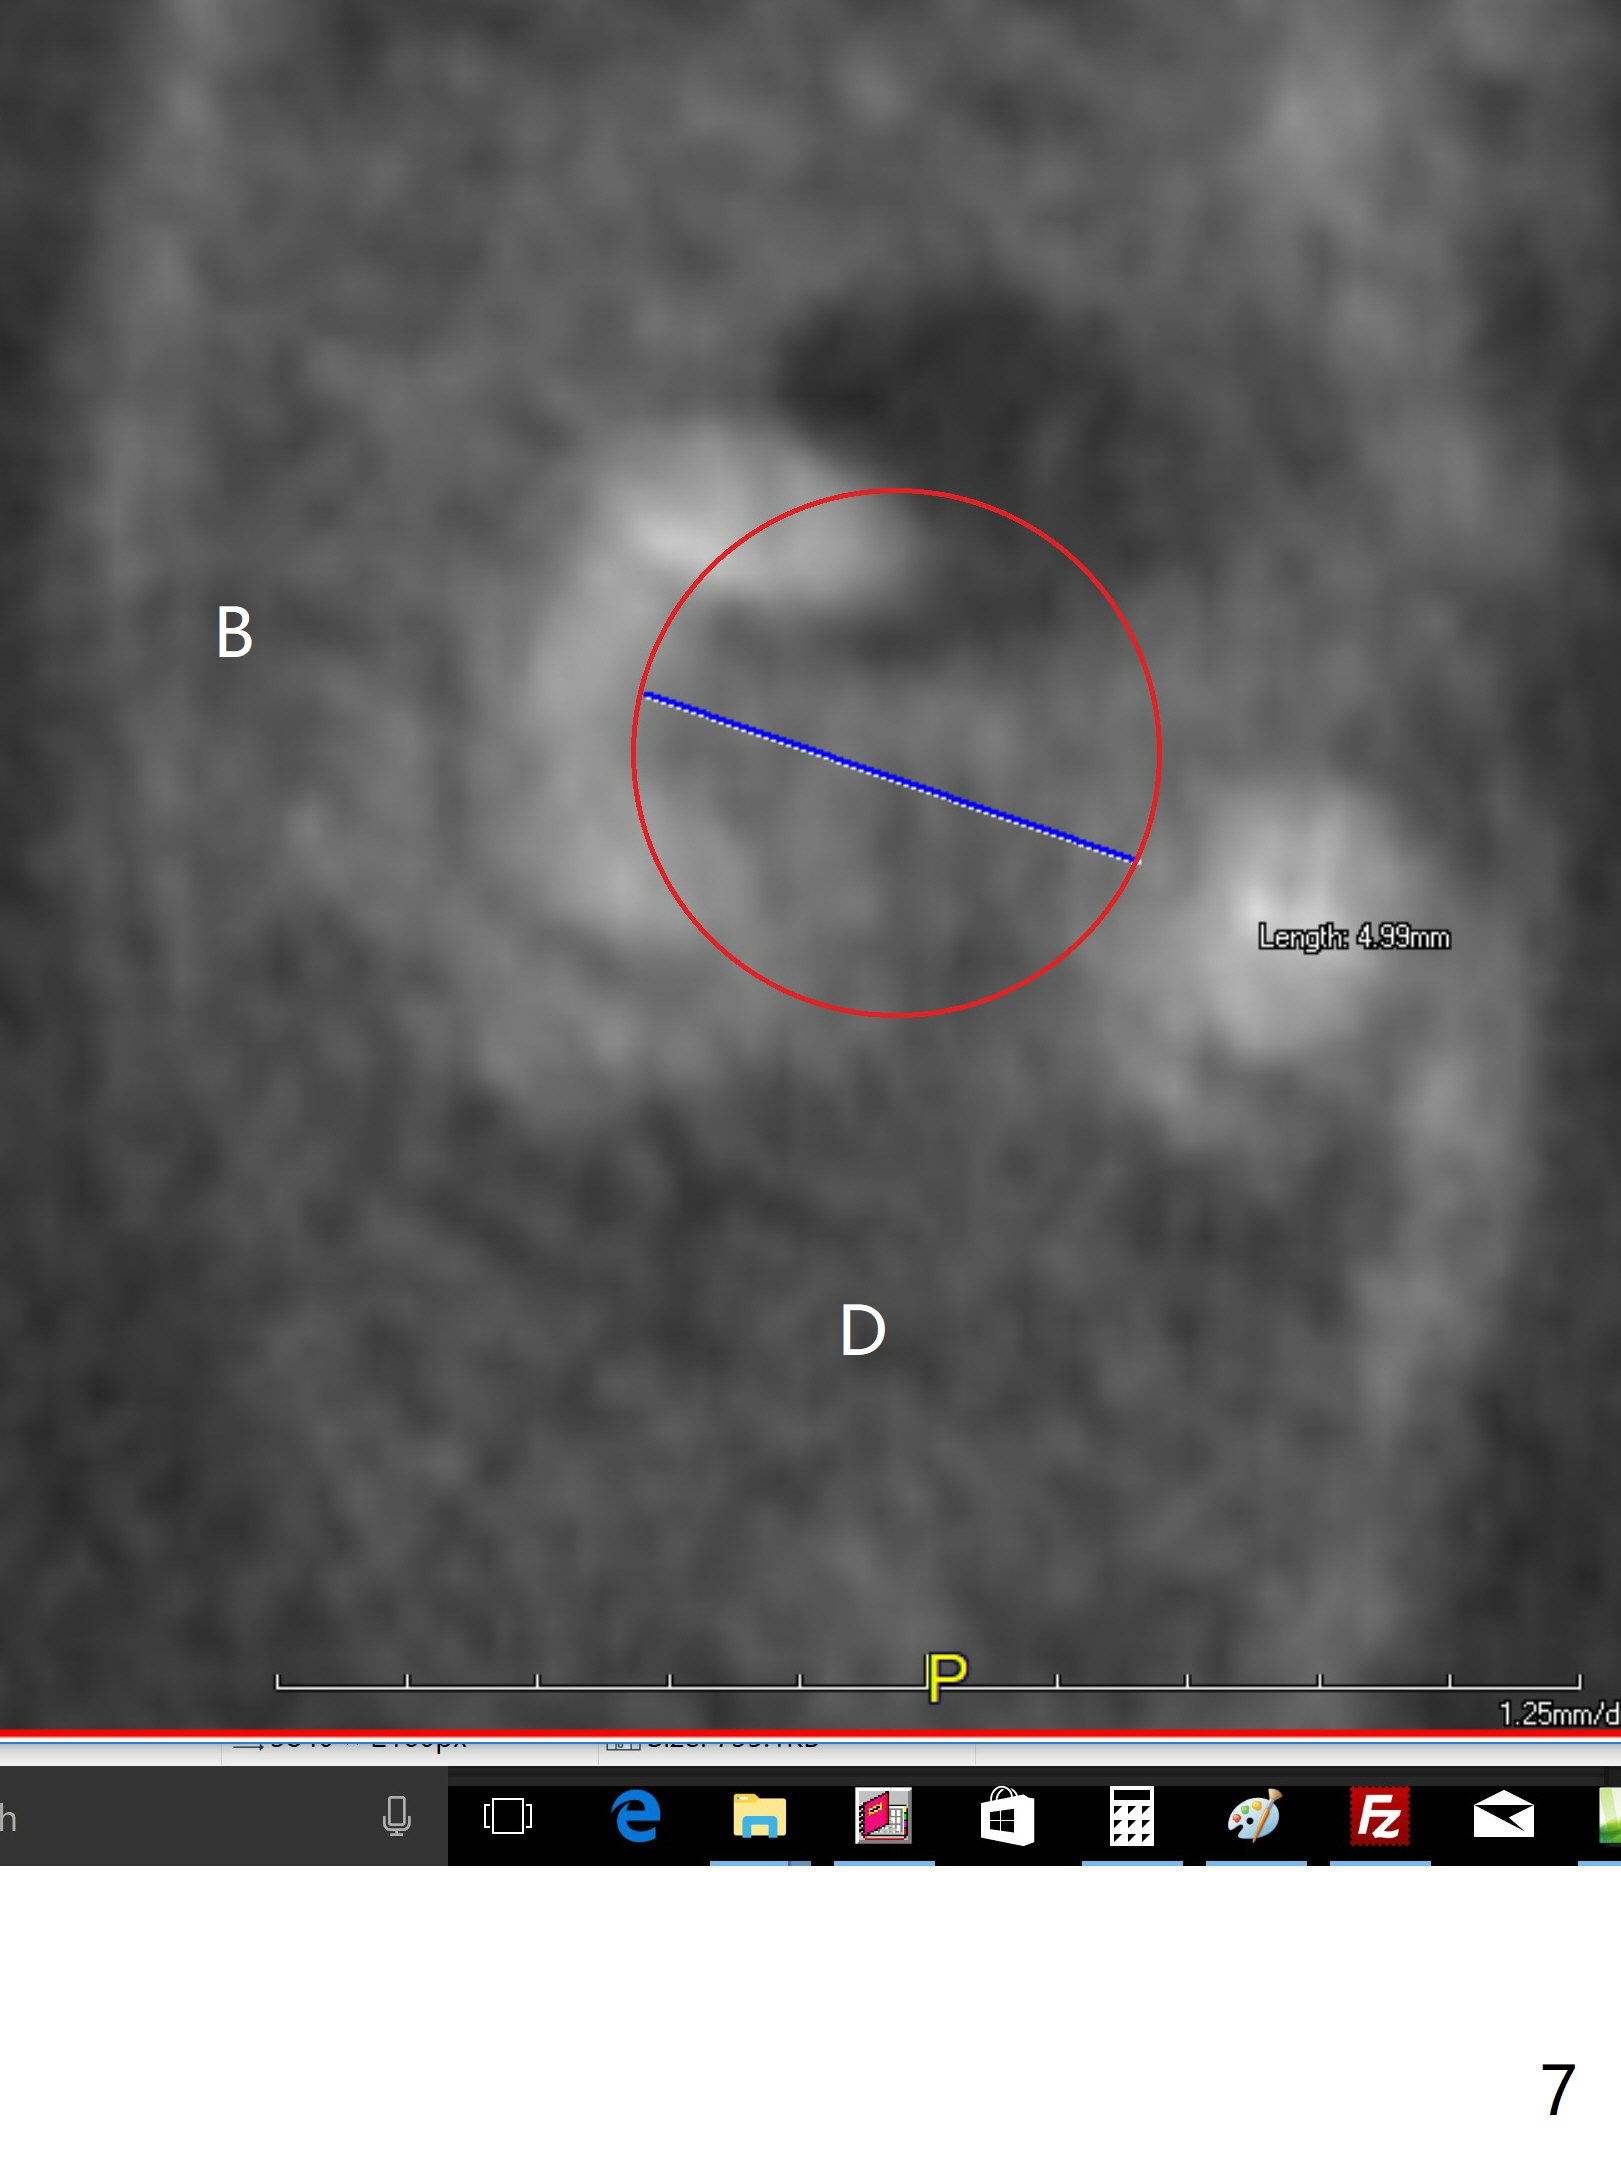

A 43-year-old woman has a failing upper right bridge (Fig.1: #2-5). While the abutment at #5 has apparently palatal open margin (Fig.2,3) and that at #4 has severe palatal bone loss (Fig.4 arrow), that at #2 has the poorest prognosis (Fig.6,7). Panoramic X-ray or PAs will be taken because of CBCT cone cut when the patient returns for #30 and 31 post-implant follow-up. Alginate impression will be taken for the upper right quadrant for provisional. The bridge will be sectioned between #3 and 5 (Fig.1 red lines) to determine salvageability of the abutments at # 4 and 5. If the latter are ok, the abutment at #2 will be extracted (expected to be loose) and implants will be placed at #2 and 3. If #4 is bad while #5 is ok, the former will be extracted and implants will be placed at #2 and 4 with a bridge. If #5 is bad while #4 is ok, implants will be placed at #2, 3 and 5.